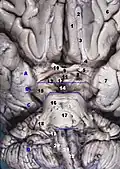

Дополнительные изображения

Глубокий разрез ствола мозга. Вид сбоку (латеральный вид). -